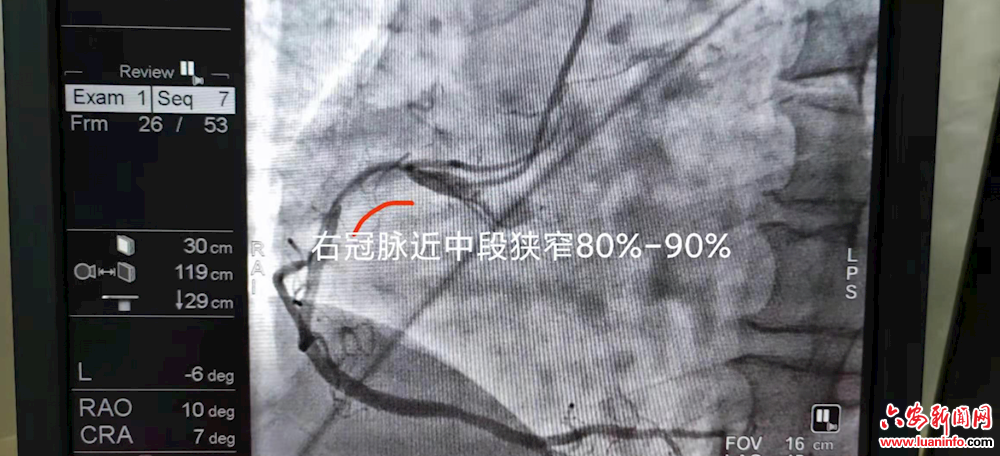

该患者因反复发作胸闷、心前区疼痛不适;既往有长期抽烟史以及高血压病史,入院后考虑冠心病,为明确诊断,7月14日,行冠脉造影检查;视频中可见其前降支中段血管狭窄达90%,且成弥漫性;右冠近段可见管状狭窄达85%;有支架植入指征,在胡主任指导下分别处理前降支及右冠,植入4枚支架,手术顺利,整个手术用时不到1小时,术后患者胸痛症状消失,且无任何不适,全程微创操作,无出血、感染等并发症,术后第三天即可痊愈出院。